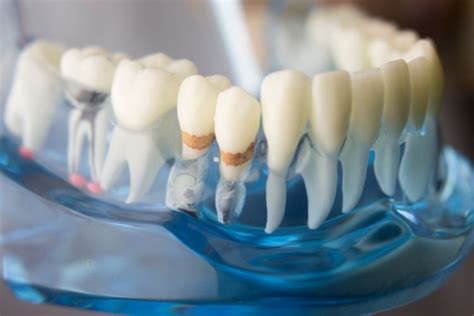

Zubný kaz

Aj psom sa v papuli môže objaviť zubný kaz. Aj tu platí, že niektoré plemená psov sú k jeho tvorbe náchylnejšie ako iné. Zubný kaz sa väčšinou tvorí na horných stoličkách a očných zuboch. Na začiatku sa javí ako mikrosieť trhliniek na povrchu zubnej skloviny. Tie sa pôsobením kyslých látok obsiahnutých v potrave postupne prehlbujú, kaz sa následne infikuje z ústnej mikroflóry a začína rozkladať poškodenú sklovinu. Ak sa poškodzovaniu zuba nezabráni ošetrením u veterinárneho lekára, zub vypadne. Včas objavený kaz sa dá zaplombovať. Ak je už v pokročilom štádiu, lekár musí zub vytrhnúť. Ak by totiž zostal aj naďalej v ústnej dutine, infikovali by sa od neho aj ostatné zuby.

U psov v porovnaní s ľuďmi je výskyt zubného kazu podstatne nižší. Hlavné dôvody sú nízky výskyt tzv. sacharidov v strave. Ak vaše psy radi maškrtia piškóty a iné sladkosti, ovocie ale aj zeleninu, môže dôjsť ku vzniku zubného kazu. Existuje malé percento psov, ktoré majú rôzne poruchy skloviny a tak sú na tvorbu kazu náchylnejšie. Kazom sa darí hlavne na zadných stoličkách.